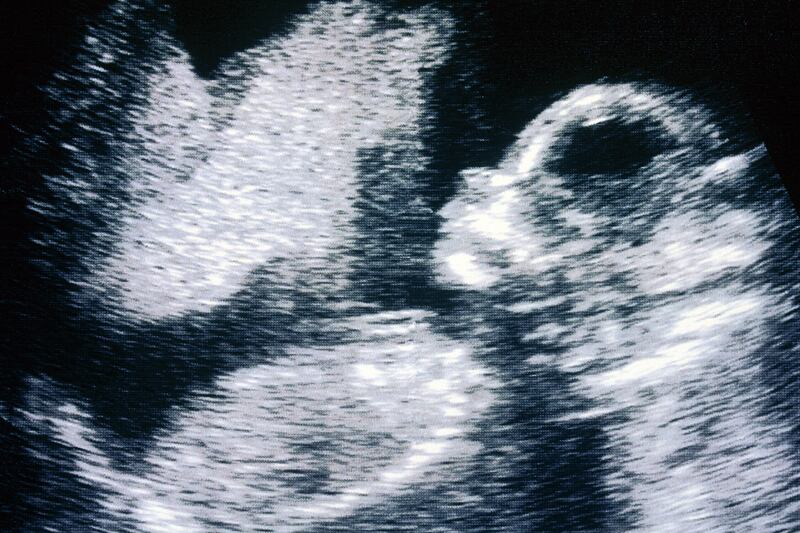

Other parts of the law includes education in public schools prioritizing birth and adoption, signs throughout health-care facilities warning against abortion “coercion,” and an order for the state health department to create and maintain a website touting alternatives to abortion and displaying images of fetuses. Also required is abortion counseling for women aiming to abort pregnancies due to fetal abnormalities, and if the abnormality is certain to be fatal, the counseling incorporates perinatal hospice information before ending the pregnancy. It reaffirms existing barriers to access, like the requirement of a notarized parental consent form for minors and a mandatory ultrasound screening within 24 hours of having an abortion.